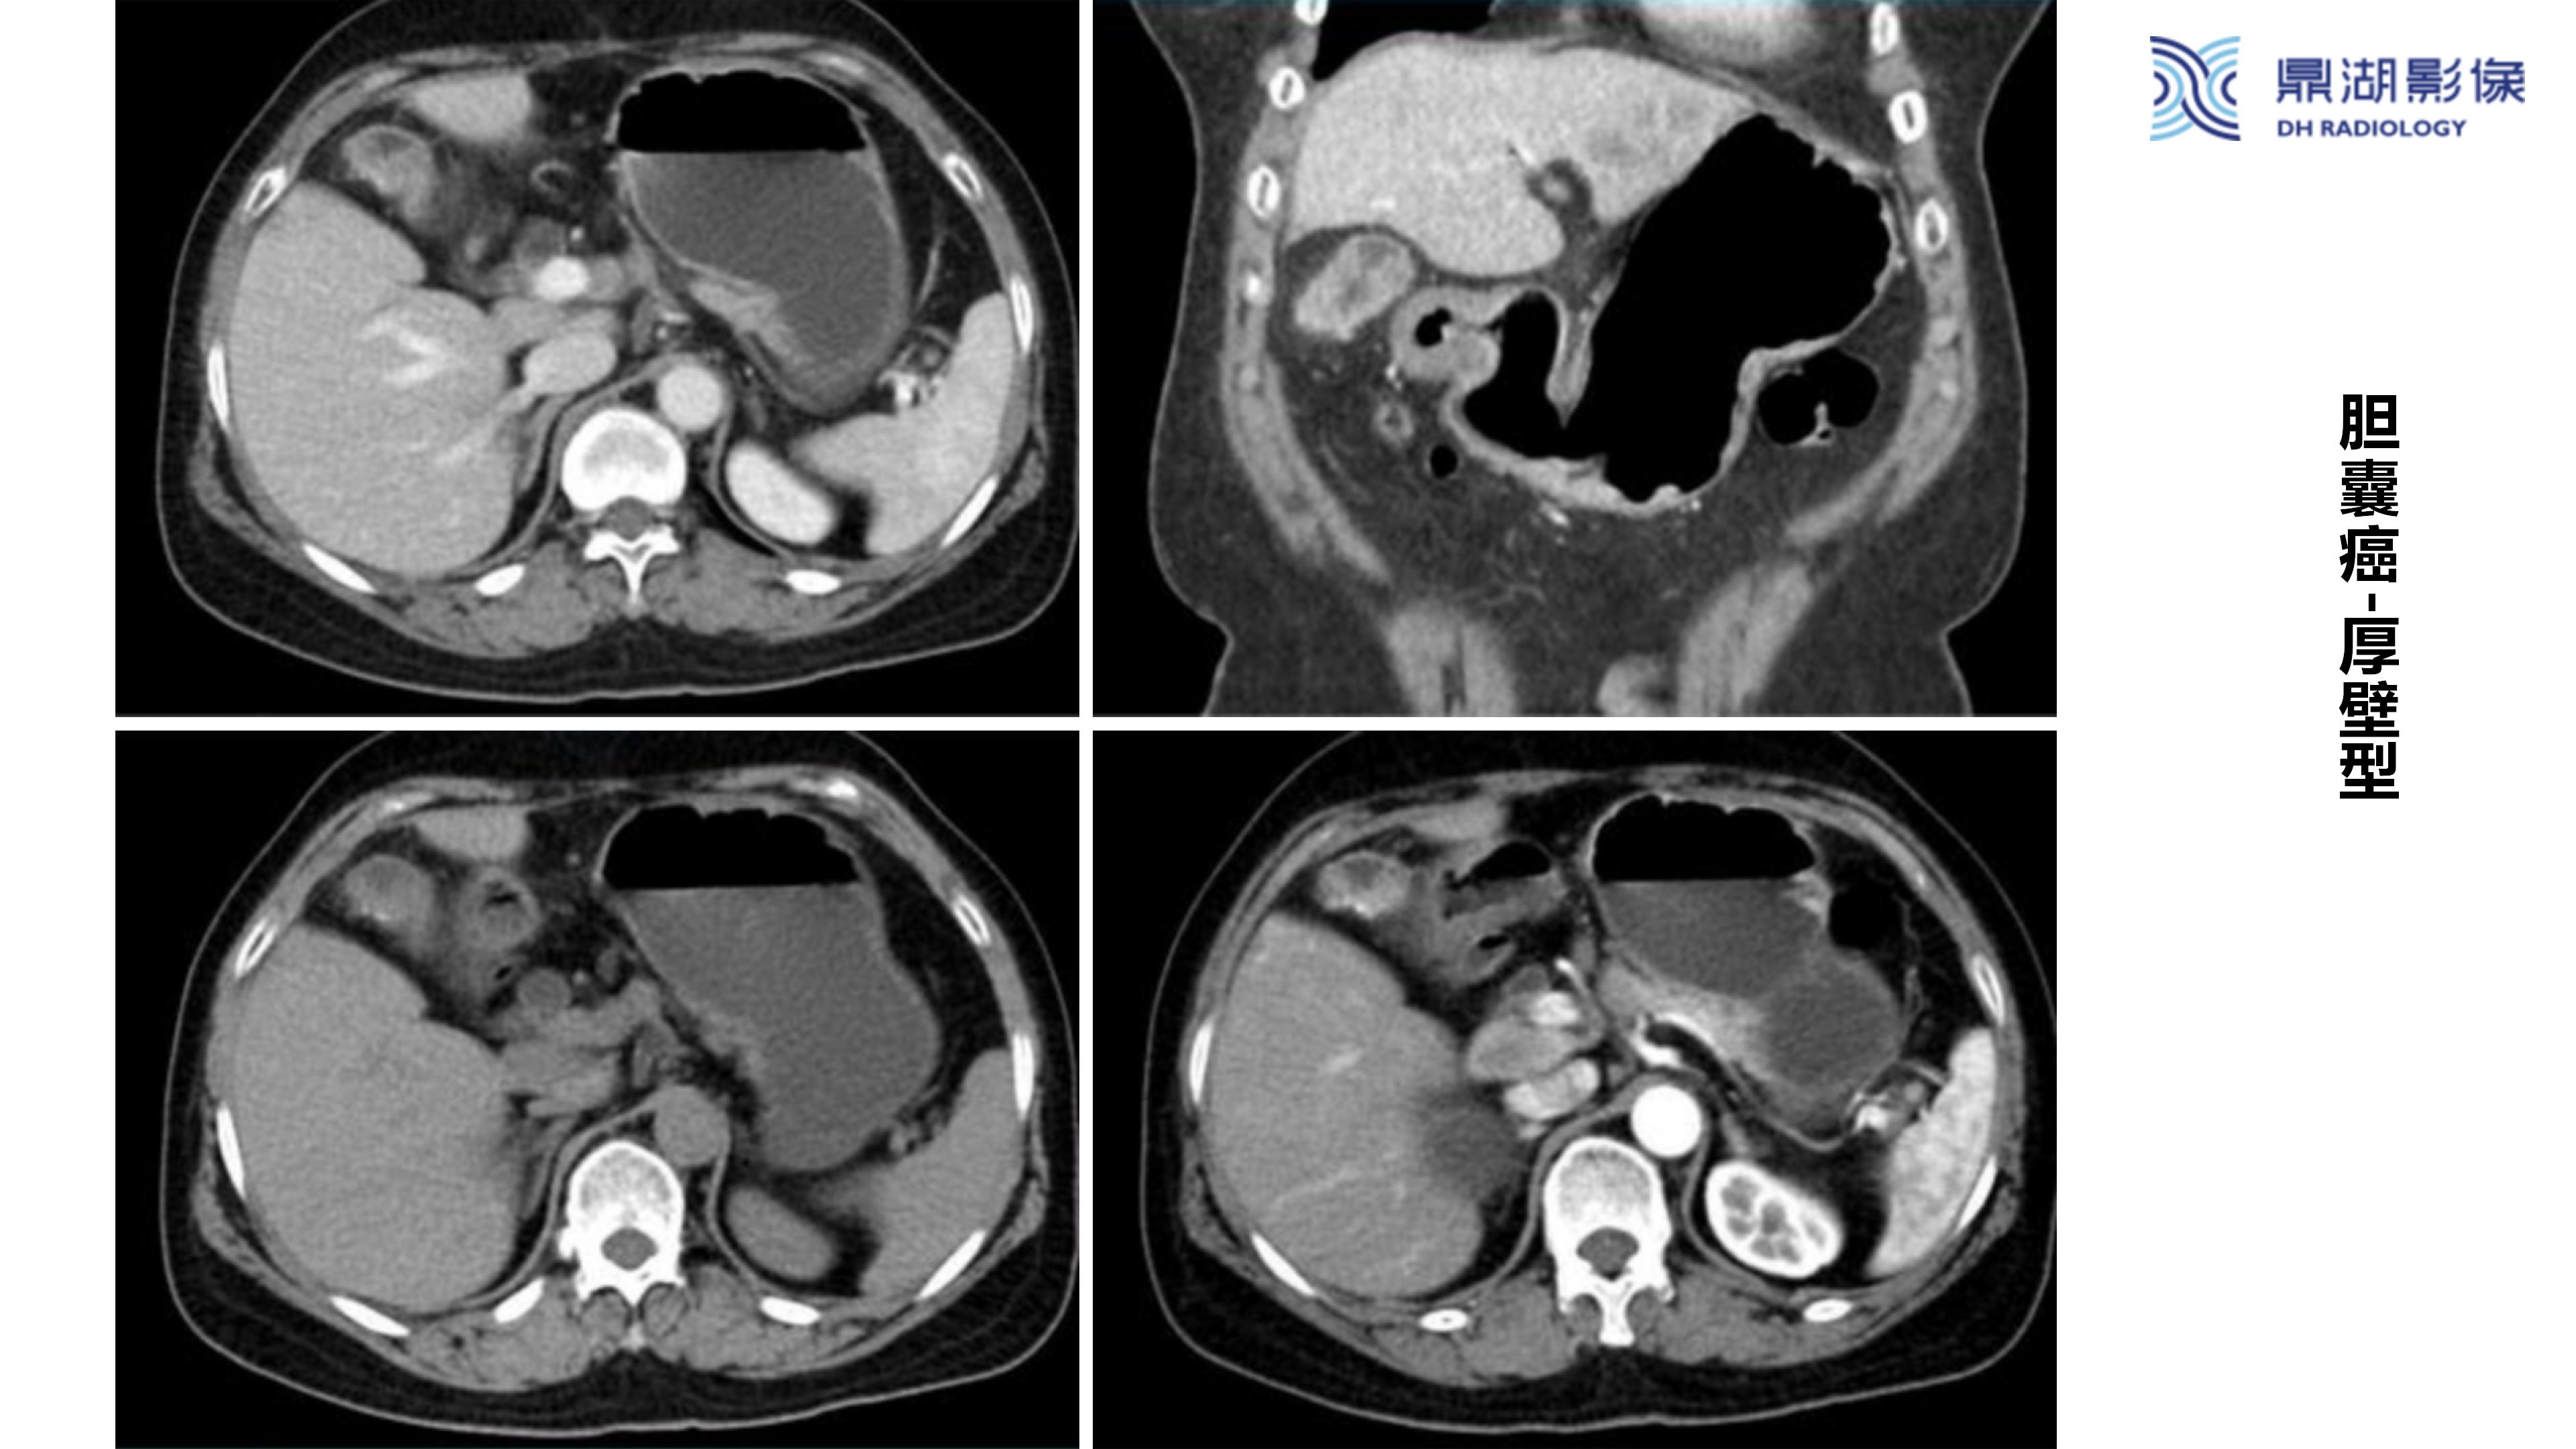

胆囊癌-鼎湖社群读片病例